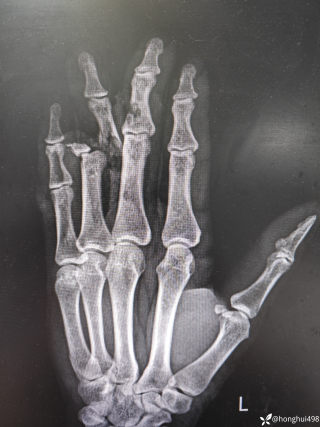

病例信息【患者信息】:男、16岁【主诉】:全身皮肤瘙痒伴皮疹10分钟【现病史及既往史】:10分钟前患者骑摩托车行驶途中,突感全身瘙痒,奇痒无比伴全身发热,心跳加快。急诊就诊,既往无类似病史,否认咽喉梗阻感、胸闷、气短、呼吸困难、恶心、呕吐、腹泻、乏力等不适。【检查】:血压:138/80mmHg,心率:116次/分,呼吸:21次/分。【临床诊断】:急性荨麻疹【治疗经过及结果】:给予吸氧、肌注扑尔敏1支,口服氯雷他定1片,静滴甲泼尼龙40mg后瘙痒明显减退,皮疹消失。病例讨论双手十指及双足未纹身,护士最后穿刺左手大拇指。